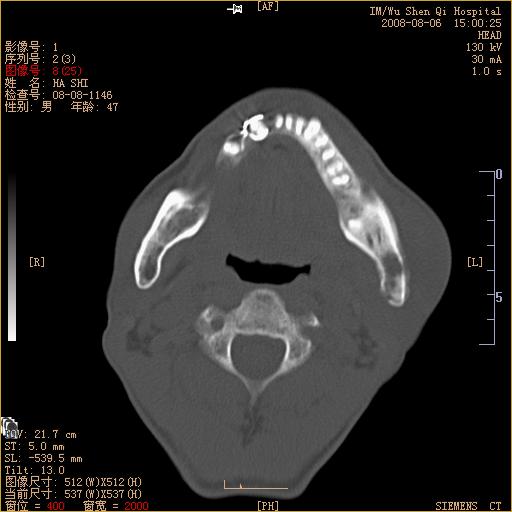

标题: CT15051:男 47岁 左下颌角部肿痛一周 [打印本页]

标题: CT15051:男 47岁 左下颌角部肿痛一周

骨质破坏,无硬化边,周围软组织肿胀,占位

左下颌骨感染性病变,牙源性可能。

左侧下颌智齿阻生。

考虑左下颌骨骨髓炎。